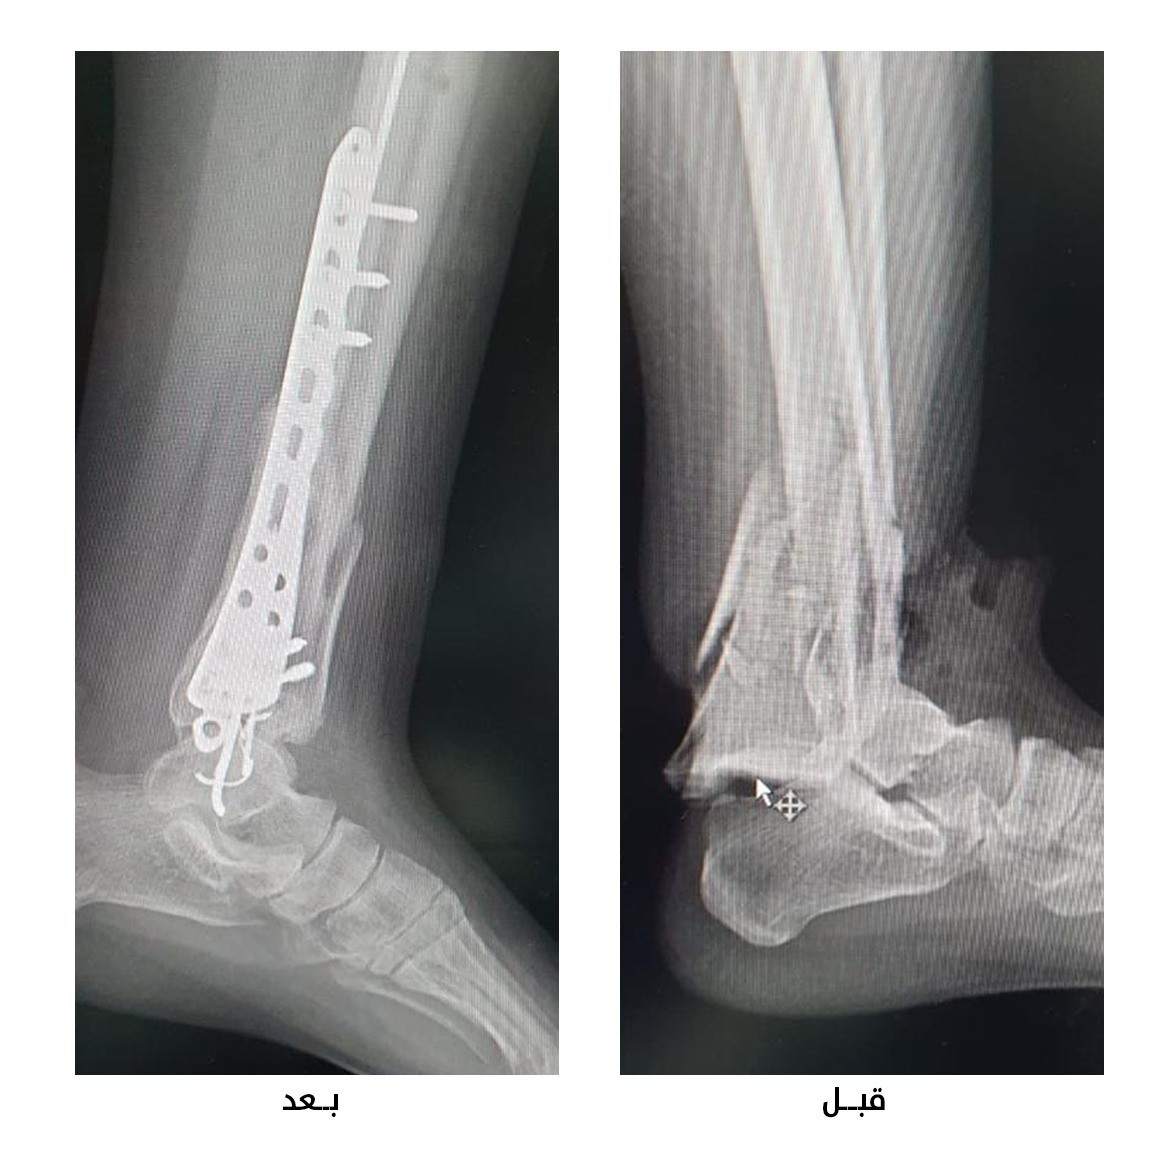

وقال تجمع القصيم الصحي أن المريضة في العقد الخامس من عمرها أُسعفت إلى طوارئ المستشفى بعد تعرضها لحادث سير أسفر عن التسبب لها بكسر مفتوح أسفل عظام الساق، مع بروز جزئي للعظم المكسور إلى خارج جلد القدم.

وأفاد التجمع أنه تم إجراء الإسعافات الأولية للمصابة ومباشرة عمل غسيل وتعقيم للكسر، قبل أن يبدأ الفريق الطبي بالتداخل الجراحي اللازم والذي كان مرحلتين على مرحلتين تضمنت المرحلة الأولى منه وضع جهاز مثبت خارجي والانتظار حتى التئام الجروح لمدة ثلاثة أسابيع، وتم في المرحلة الثانية تثبيت كسر الكاحل بشريحة ومسامير طبية خاصة.

وبيّن تجمع القصيم أن المصابة أدخلت بعد الجراحة الثانية بشهرين في برنامج التأهيل والعلاج الطبيعي، مؤكداً أن المرأة وبعد مضى ستة أشهر على العملية الجراحية والتأهيل استعادت عافيتها الكاملة وأصبحت تستطيع المشي على قدميها دون الحاجة لعكازات أو مساعده من أحد، مع مجال حركة جيد لمفصل الكاحل.